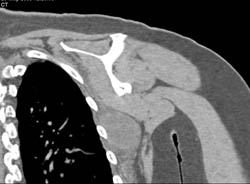

Fracture Through SI Joint